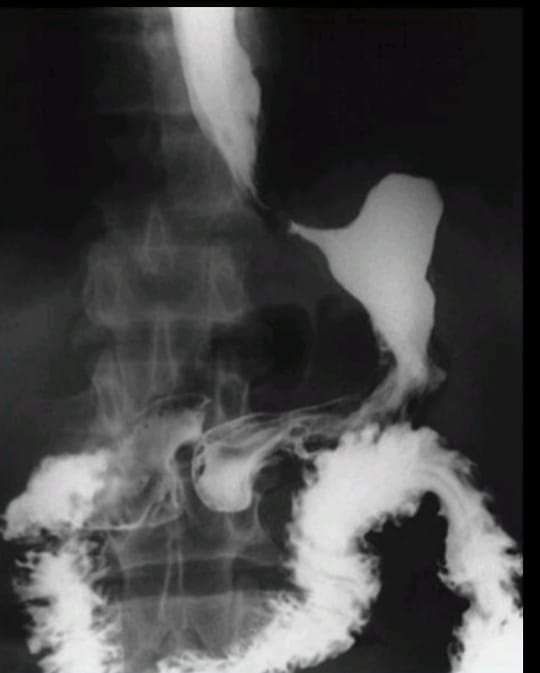

linitis plastica

A rare type of stomach cancer that begins in the lining of the stomach and spreads to the muscles of the stomach wall. This causes the wall of the stomach to become thick, hard, and rubbery, which leads to trouble digesting food.